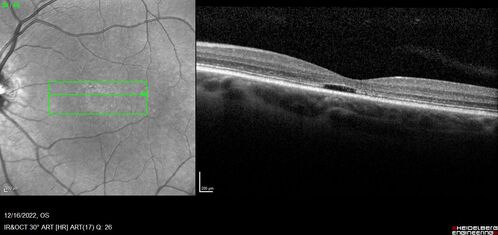

Stargardt Disease - Very Mild - 24 year old

This patient has 3 different ABCA4 mutations. His mother and sister have stargardts and his father has RP. His sisters images are also on Retinagallery.com

Stargardt Sibling - ABCA4 3 mutations